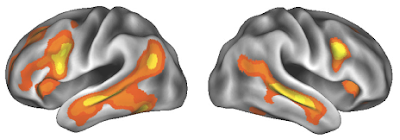

Hace pocos días se publicaba en la prestigiosa revista Nature Neuroscience un estudio liderado por investigadoras catalanas (de la Universitat Autònoma de Barcelona), que reflejaba por primera vez los cambios que provoca la maternidad a nivel cerebral. Estos cambios están dirigidos a mejorar la capacidad de la madre para vincularse con el bebé. Para ello, compararon imágenes de resonancia magnética de 25 gestantes primíparas antes y después del parto, de las parejas hombres de 19 de ellas y de un grupo control formado por 20 mujeres que nunca habían estado embarazadas. Los resultados muestran una reducción en determinadas zonas de la sustancia gris (corteza cerebral) de las mujeres que viven su primer embarazo, áreas que los neurocientíficos relacionan con las relaciones sociales. El estudio incluía a su vez, mujeres gestantes que habían seguido tratamientos de fertilidad y también se observaban dichos cambios, pero no en los hombres. La reducción que se produce en la materia gris no significa una pérdida de funciones ni de memoria. En realidad es más una selección de las mejores conexiones neuronales, como sucede en la adolescencia, una reestructuración cerebral con fines adaptativos, que se mantiene al menos hasta dos años después del parto. Qué sucede después, si se mantiene o vuelve al estado anterior al embarazo, necesita futuros estudios.

Hace pocos días se publicaba en la prestigiosa revista Nature Neuroscience un estudio liderado por investigadoras catalanas (de la Universitat Autònoma de Barcelona), que reflejaba por primera vez los cambios que provoca la maternidad a nivel cerebral. Estos cambios están dirigidos a mejorar la capacidad de la madre para vincularse con el bebé. Para ello, compararon imágenes de resonancia magnética de 25 gestantes primíparas antes y después del parto, de las parejas hombres de 19 de ellas y de un grupo control formado por 20 mujeres que nunca habían estado embarazadas. Los resultados muestran una reducción en determinadas zonas de la sustancia gris (corteza cerebral) de las mujeres que viven su primer embarazo, áreas que los neurocientíficos relacionan con las relaciones sociales. El estudio incluía a su vez, mujeres gestantes que habían seguido tratamientos de fertilidad y también se observaban dichos cambios, pero no en los hombres. La reducción que se produce en la materia gris no significa una pérdida de funciones ni de memoria. En realidad es más una selección de las mejores conexiones neuronales, como sucede en la adolescencia, una reestructuración cerebral con fines adaptativos, que se mantiene al menos hasta dos años después del parto. Qué sucede después, si se mantiene o vuelve al estado anterior al embarazo, necesita futuros estudios.

Fa pocs dies es publicava a la prestigiosa revista Nature Neuroscience un estudi liderat per investigadores catalanes (de la Universitat Autònoma de Barcelona), que reflectia per primera vegada els canvis que provoca la maternitat a nivell cerebral. Aquests canvis estan dirigits a millorar la capacitat de la mare per vincular-se amb el nadó. Per a això, van comparar imatges de ressonància magnètica de 25 gestants primípares abans i després del part, de les parelles homes de 19 d'elles i d'un grup control format per 20 dones que mai havien estat embarassades. Els resultats mostren una reducció en determinades zones de la substància grisa (escorça cerebral) de les dones que viuen el seu primer embaràs, àrees que els neurocientífics relacionen amb les relacions socials. L'estudi incloïa al seu torn, dones gestants que havien seguit tractaments de fertilitat i també s'observaven aquests canvis, però no en els homes. La reducció que es produeix en la matèria grisa no significa una pèrdua de funcions ni de memòria. En realitat és més una selecció de les millors connexions neuronals, com succeeix en l'adolescència, una reestructuració cerebral amb fins adaptatius, que es manté almenys fins a dos anys després del part. Què passa després, si es manté o torna a l'estat anterior a l'embaràs, necessita de futurs estudis.

Fa pocs dies es publicava a la prestigiosa revista Nature Neuroscience un estudi liderat per investigadores catalanes (de la Universitat Autònoma de Barcelona), que reflectia per primera vegada els canvis que provoca la maternitat a nivell cerebral. Aquests canvis estan dirigits a millorar la capacitat de la mare per vincular-se amb el nadó. Per a això, van comparar imatges de ressonància magnètica de 25 gestants primípares abans i després del part, de les parelles homes de 19 d'elles i d'un grup control format per 20 dones que mai havien estat embarassades. Els resultats mostren una reducció en determinades zones de la substància grisa (escorça cerebral) de les dones que viuen el seu primer embaràs, àrees que els neurocientífics relacionen amb les relacions socials. L'estudi incloïa al seu torn, dones gestants que havien seguit tractaments de fertilitat i també s'observaven aquests canvis, però no en els homes. La reducció que es produeix en la matèria grisa no significa una pèrdua de funcions ni de memòria. En realitat és més una selecció de les millors connexions neuronals, com succeeix en l'adolescència, una reestructuració cerebral amb fins adaptatius, que es manté almenys fins a dos anys després del part. Què passa després, si es manté o torna a l'estat anterior a l'embaràs, necessita de futurs estudis.